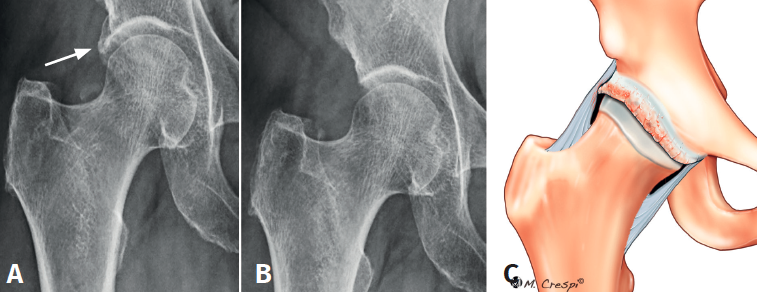

(A4) Osificación circunferencial completa del labrum contiguo al borde lateral del borde acetabular

- Características y morfología radiográfica: osificación circunferencial del labrum, menos redondeada y contigua con el borde lateral del borde acetabular. No tiene línea radiolúcida medial, a diferencia de las otras calcificaciones descritas previamente. La tomografía axial computarizada (TAC) revela el “signo de doble borde” del acetábulo y la imagen tridimensional de la reconstrucción por TAC revela un engrosamiento del borde acetabular, hallazgos que orientan a la osificación del labrum. Estos pacientes tienen un excelente mantenimiento del espacio articular y del cartílago articular (al menos 2 mm de espacio articular en las radiografías) y ningún daño o daño de bajo grado del cartílago en la artroscopia. La falta de osteofitos o degeneración articular avanzada apoya la afirmación de que este tipo de osificación es un proceso separado de los osteofitos acetabulares(5)(Figura 5).

- Localización y lesiones asociadas: estos pacientes representan un subgrupo de CFA de tipo pincer, generalmente anterolateral y tienen más probabilidades de ser mayores, mujeres y tener síntomas más graves(5).

- Tratamiento: la cirugía (abierta o artroscópica) se puede utilizar para la escisión de este tipo de calcificación con una expectativa razonable de mejoría de los síntomas. En casos de remanente labral, este es separado cuidadosamente del resto de la porción osificada mediante uso de bisturí artroscópico o radiofrecuencia. A continuación, se procede a la extirpación de la porción osificada del labrum (acetabuloplastia) con una fresa de 5,5 mm y finalmente, si el resto labral es suficiente, se procede a su reparación. Habitualmente y debido al daño importante o la funcionalidad escasa del labrum tras la extirpación, en nuestra experiencia asociamos generalmente la técnica de aumento o de reconstrucción labral(6).